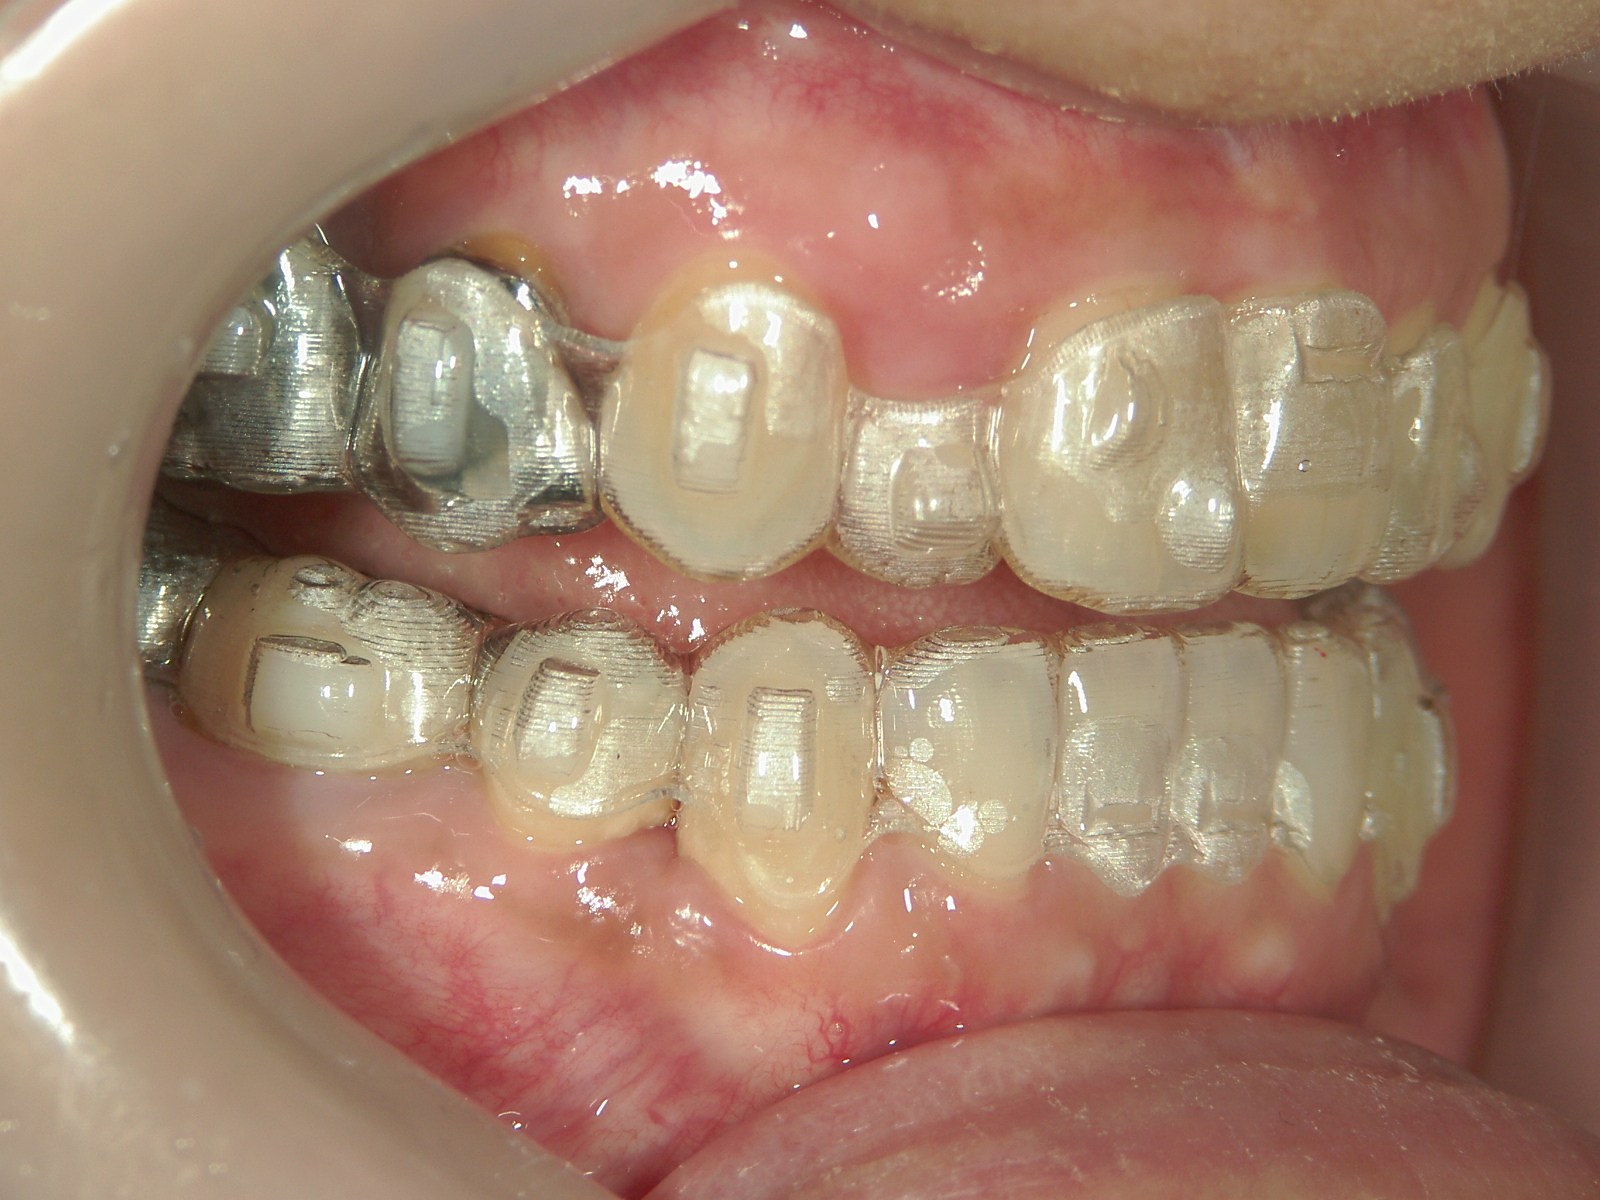

①患者様はインビザライン矯正をご希望でしたが、上顎骨が小さく、受け口になっているので、インビザライン矯正で治療するために「骨切断OPE」「矯正装置(MSE+フェイスマスク)」で上顎骨を拡大しました。

②右上前歯が内側に入っているため、歯列に入る隙間を作るためにワイヤー矯正を併用し、右上前歯を出しました。

③矯正装置を除去し、インビザライン矯正で歯列を整えました。